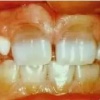

Diasteem – vahe esimeste hammaste vahel. Esineb 50%-l 6-8 aastastel lastel. Kuni 2 mm diasteemi puhul on, peale lateraalse intsisiivi ja silmahamba lõikumist, võimalik diasteemi iseeneslik sulgumine. Diasteem, mille suurus...